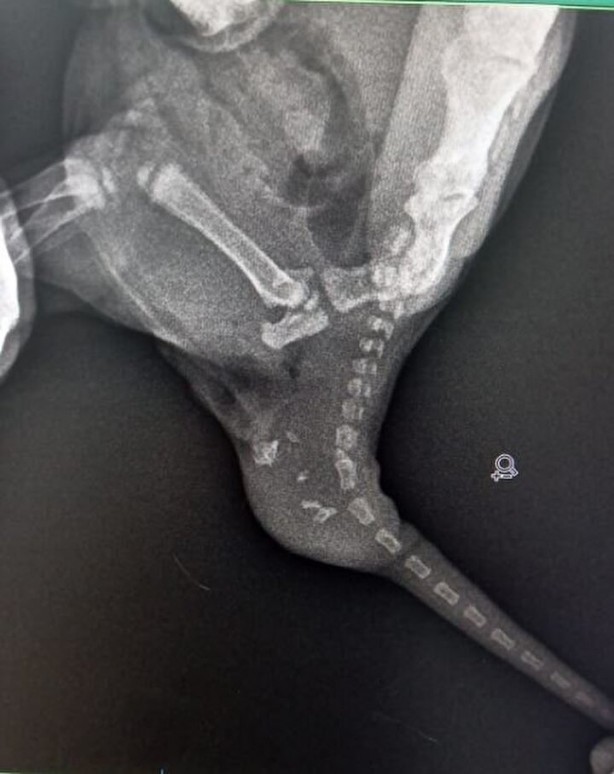

Doğan 2 yavru kediden birinin kuyruğunda şişlik olduğunu fark eden Yıldız, veterinere başvurdu. Veterinerde yapılan kontrolde kedinin kuyruğunda; dişleri, tüyleri, iskelet sistemi, kanal hücreleri oluşan yavru taşıdığı ortaya çıktı. Yavru kediye 'teratom' (canavar tümör) tanısı konuldu. Kedi cerrahi operasyona alınarak, tümör temizlendi. Şu an 4 aylık olan kedi, sağlığına kavuştu.

'DÜNYADA BİLİNEN İKİNCİ VAKA' Ameliyatı gerçekleştiren veteriner hekimlerden Emir Düzgören, kedi ile ilgili vaka bildirim raporu hazırlayacaklarını belirterek, "Yavruyu anesteziye uygun hale geldiğinde röntgene aldık ve içeride kemik benzeri dokular olduğu tespit edildi. Ardından çocuğun kuyruğunun alt bölümüne teratom tanısı konuldu. Çoğalan hücrelerden birinin bir tümör hücresine dönüşmesi sonucu oluşmuş. Bu çocukta hem deri, kıl, kemik, kanal hücrelerinin tamamı gelişen canavar tümör oluşmuş. Kardeşi gibi düşünebiliriz; ama tıbbi olarak aslında bir tümör.